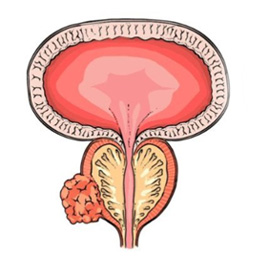

ξΎΟ≈Α© «ΖΔ…ζ‘ΎξΎΟ≈≤ΩΈΜΒΡΕώ–‘÷ΉΝωΘ§’β“Μ«χ”ρΈΜ”Ύ ≥Ιήœ¬ΕΥ”κΈΗΫΜΫγ¥ΠΘ§ «ΈΗ ≥ΙήΝ§Ϋ”ΒΡΙΐΕ…ΕΈΓΘ”…”ΎΤδΫβΤ ΈΜ÷ΟΧΊ βΘ§ξΎΟ≈Α©Φ»ΨΏ”– ≥ΙήΑ©ΒΡΡ≥–©ΧΊΒψΘ§“≤”κΈΗΑ©”–œύΥΤ÷°¥ΠΓΘΝΥΫβξΎΟ≈Α©ΒΡ≤Γ“ρΓΔ÷ΔΉ¥ΓΔ’οΕœΚΆ÷ΈΝΤΖΫΖ®Θ§”–÷ζ”ΎΧαΗΏ‘γΤΎΖΔœ÷ΚΆ÷ΈΝΤ–ßΙϊΓΘ